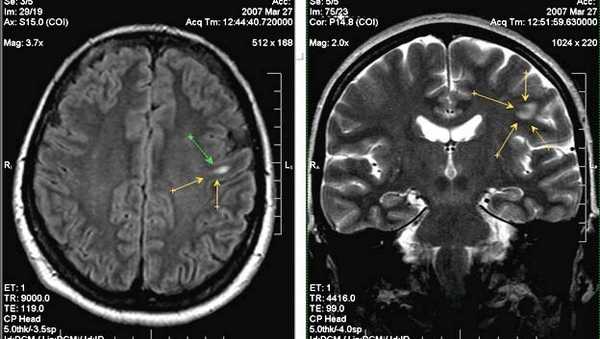

На вскрытии обнаруживают расширение желудочков мозга и его атрофию в результате гибели нейронов. Гистологически выявляются пенистые гистиоциты в костном мозге, печени, селезенке, лимфатических узлах и др.

Ганглиозидоз GM1 тип I

GM1-ганглиозидоз тип I (генерализованный семейный ганглиозидоз, нейровисцеральный липидоз, недостаточность b-галактозидазы) характеризуется аутосомно-рецессивно наследуемой недостаточностью фермента GM1-b-галактозадазы. Активность этого фермента в головном мозге, печени и фибробластах кожи больного снижена до 0,1% нормы. Описано более 100 случаев заболевания.

В основе болезни лежит мутация структурного гена, кодирующего мономерный полипептид A1GM1-b-галактозидазы и локализованного на коротком плече 3-й хромосомы (p12q21). При этом дефекте нарушено отщепление концевой галактозы от GM1-ганглиозида, который откладывается в больших количествах в сером веществе головного мозга и печени.

GM1-ганглиозидоз обнаруживается при рождении или вскоре после него. Отмечаются плохой аппетит, слабость сосания и крика, недостаточная прибавка в весе, отечность нижних конечностей, мышечная гипотония и малая активность ребенка (спокоен, большую часть времени спит). Гепатоспленомегалия наблюдается с первых месяцев жизни. Часто встречаются дорсолюмбальный сколиоз, нерезкое увеличение размеров суставов, укорочение и утолщение пальцев (брахидактилия). Рентгенографически определяется множественный дизостоз. Характерны частые бронхопневмонии. Развиваются клонико-тонические судороги, Примерно у 50% больных с рано развившимся GM1-ганглиозидозом наблюдаются вишнево-красные пятна на глазном дне в области желтого пятна, образовавшиеся в результате отложения ганглиозидов в клетках сетчатки. Если ребенок дожил до 6 месяцев, то у него формируется характерный внешний вид (выступающие лобные бугры, запавшая переносица, большие низко расположенные ушные раковины, гипертрофия десен, макроглоссия, отек лица).